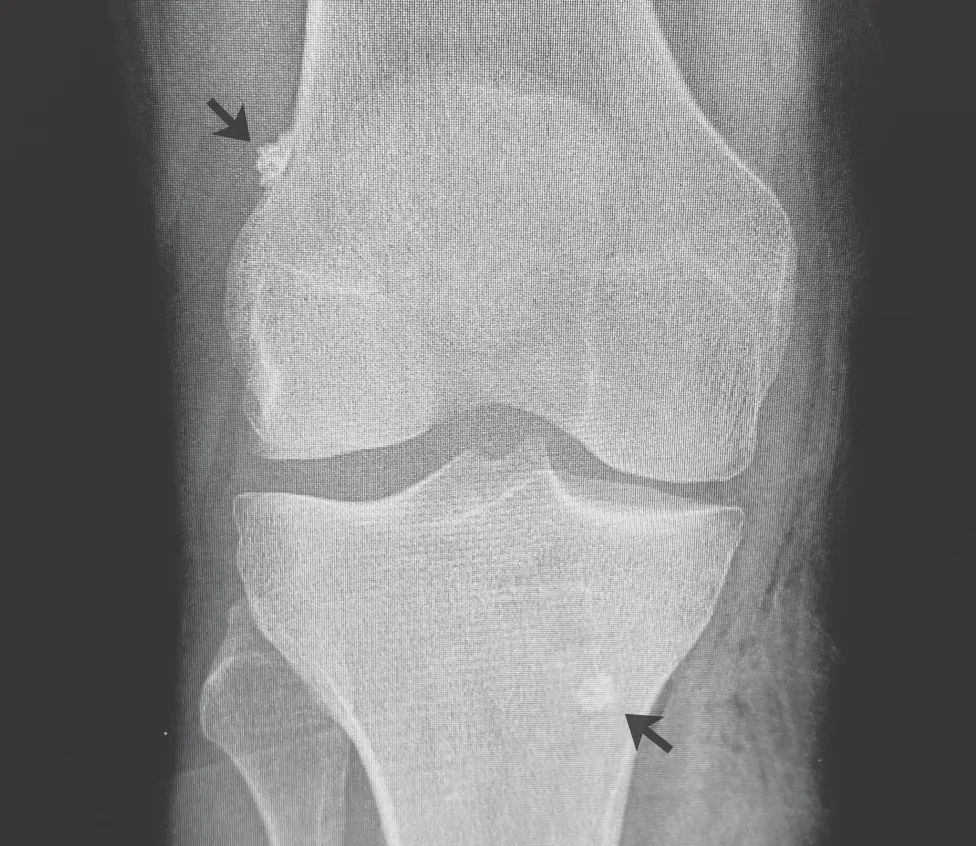

During ACL repair, the ligament is reattached to the bone. However, only certain types of ACL tears can be repaired. In addition to tear location on the ACL, your time between injury and treatment is a big factor in whether your ACL can be repaired.4

Your doctor will determine the best treatment for you based on the tear location and other factors. ACL repair, a procedure that reattaches the torn ligament to the femur bone, may be the right treatment. If ACL repair is not possible, your surgeon will likely perform an ACL reconstruction, which removes the damaged ligament and replaces it with a graft.